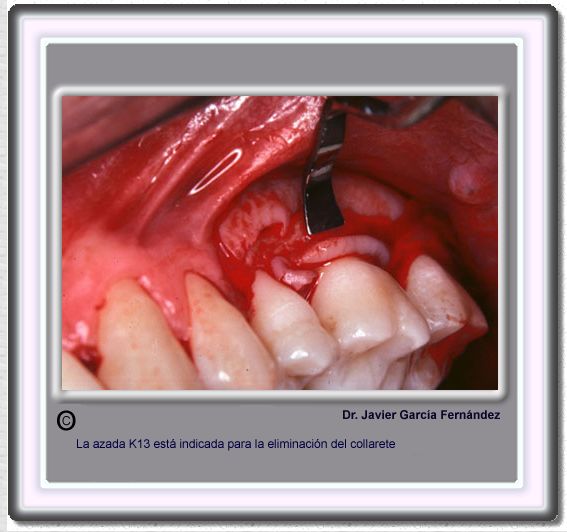

image 496